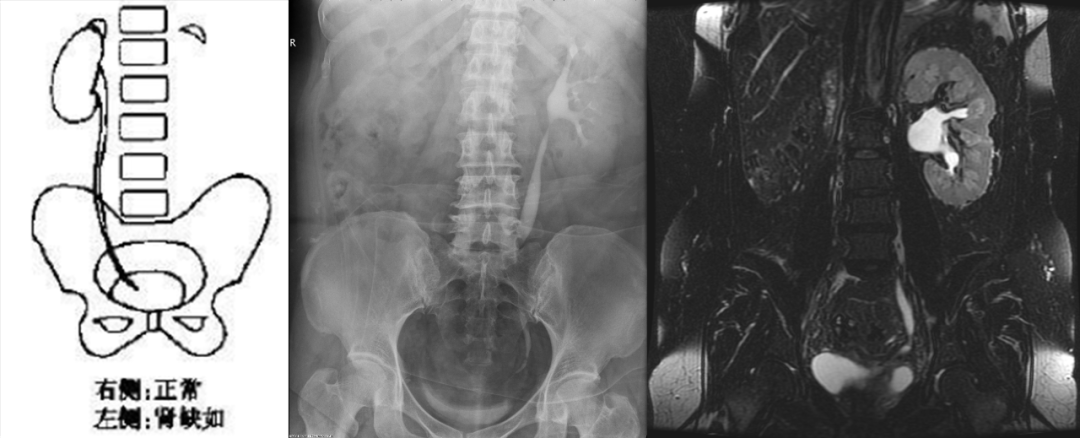

肾数目异常

肾缺如(孤立肾)

由于一侧肾组织和输尿管芽不发育,或仅有残缺的后肾组织所致单侧肾缺如常伴同侧输尿管缺如

对侧肾脏可呈代偿性肥大,可伴有旋转不良或异位

需鉴别:异位肾、先天性肾发育不良(侏儒肾)、手术后肾缺如